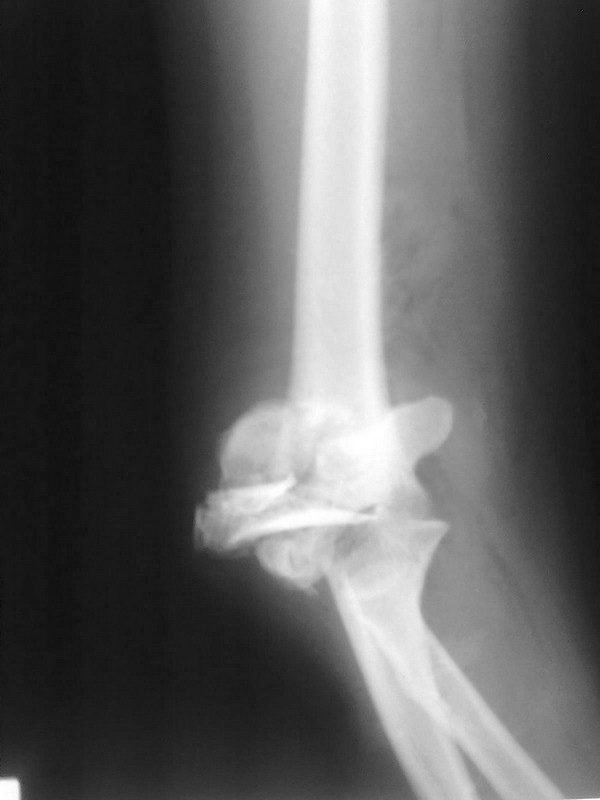

Уважаемые коллеги. Помогите советом определится с тактикой дальнейшего лечения. Пациентка, 16 лет. В 02.2011 - тяжелая сочетанная травма ОДА, груди, живота. В т.ч.открытый многооскольчатый чрезмыщелковй перелом правого плеча и локтевого отростка

Имя     : 2011 800.jpg

Тип     : image/jpg

Размер  : 68438 байтов

Описание: отсутствует

Url     : http://weborto.net:8080/pipermail/ortho/attachments/20120313/c909356e/attachment-0007.jpg